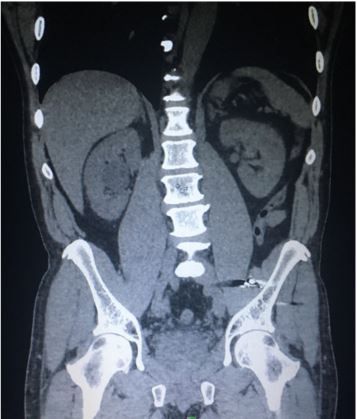

Imaging: See CT scan image